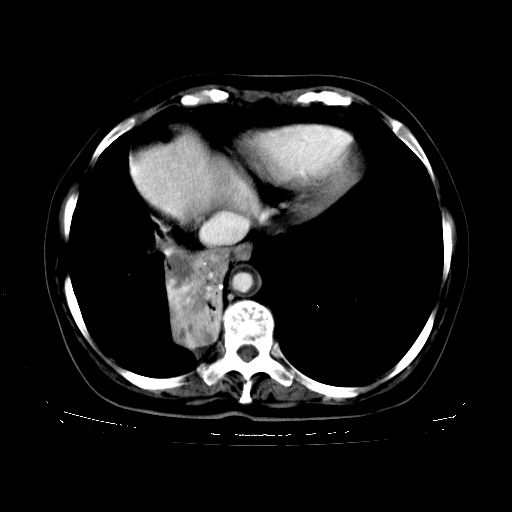

标题: CT23067:女,70岁,咳嗽、咳痰一个月,低热一周。 [打印本页]

女,70岁,咳嗽、咳痰一个月,低热一周。

1.左上肺结核,部分纤维化。右肺中下叶部分肺不张,内见液化、坏死及点状钙化,右中下叶支气管壁增厚、管腔狭窄,见多个点状钙化,结合临床考虑支气管内膜结核,建议痰检查抗酸杆菌并参考血沉。两肺多个小圆点状高密度灶,境界模糊,多考虑结核肺内播散。但本人年龄较大首先应支气管镜检以除外右肺癌。

2.胸主动脉夹层。